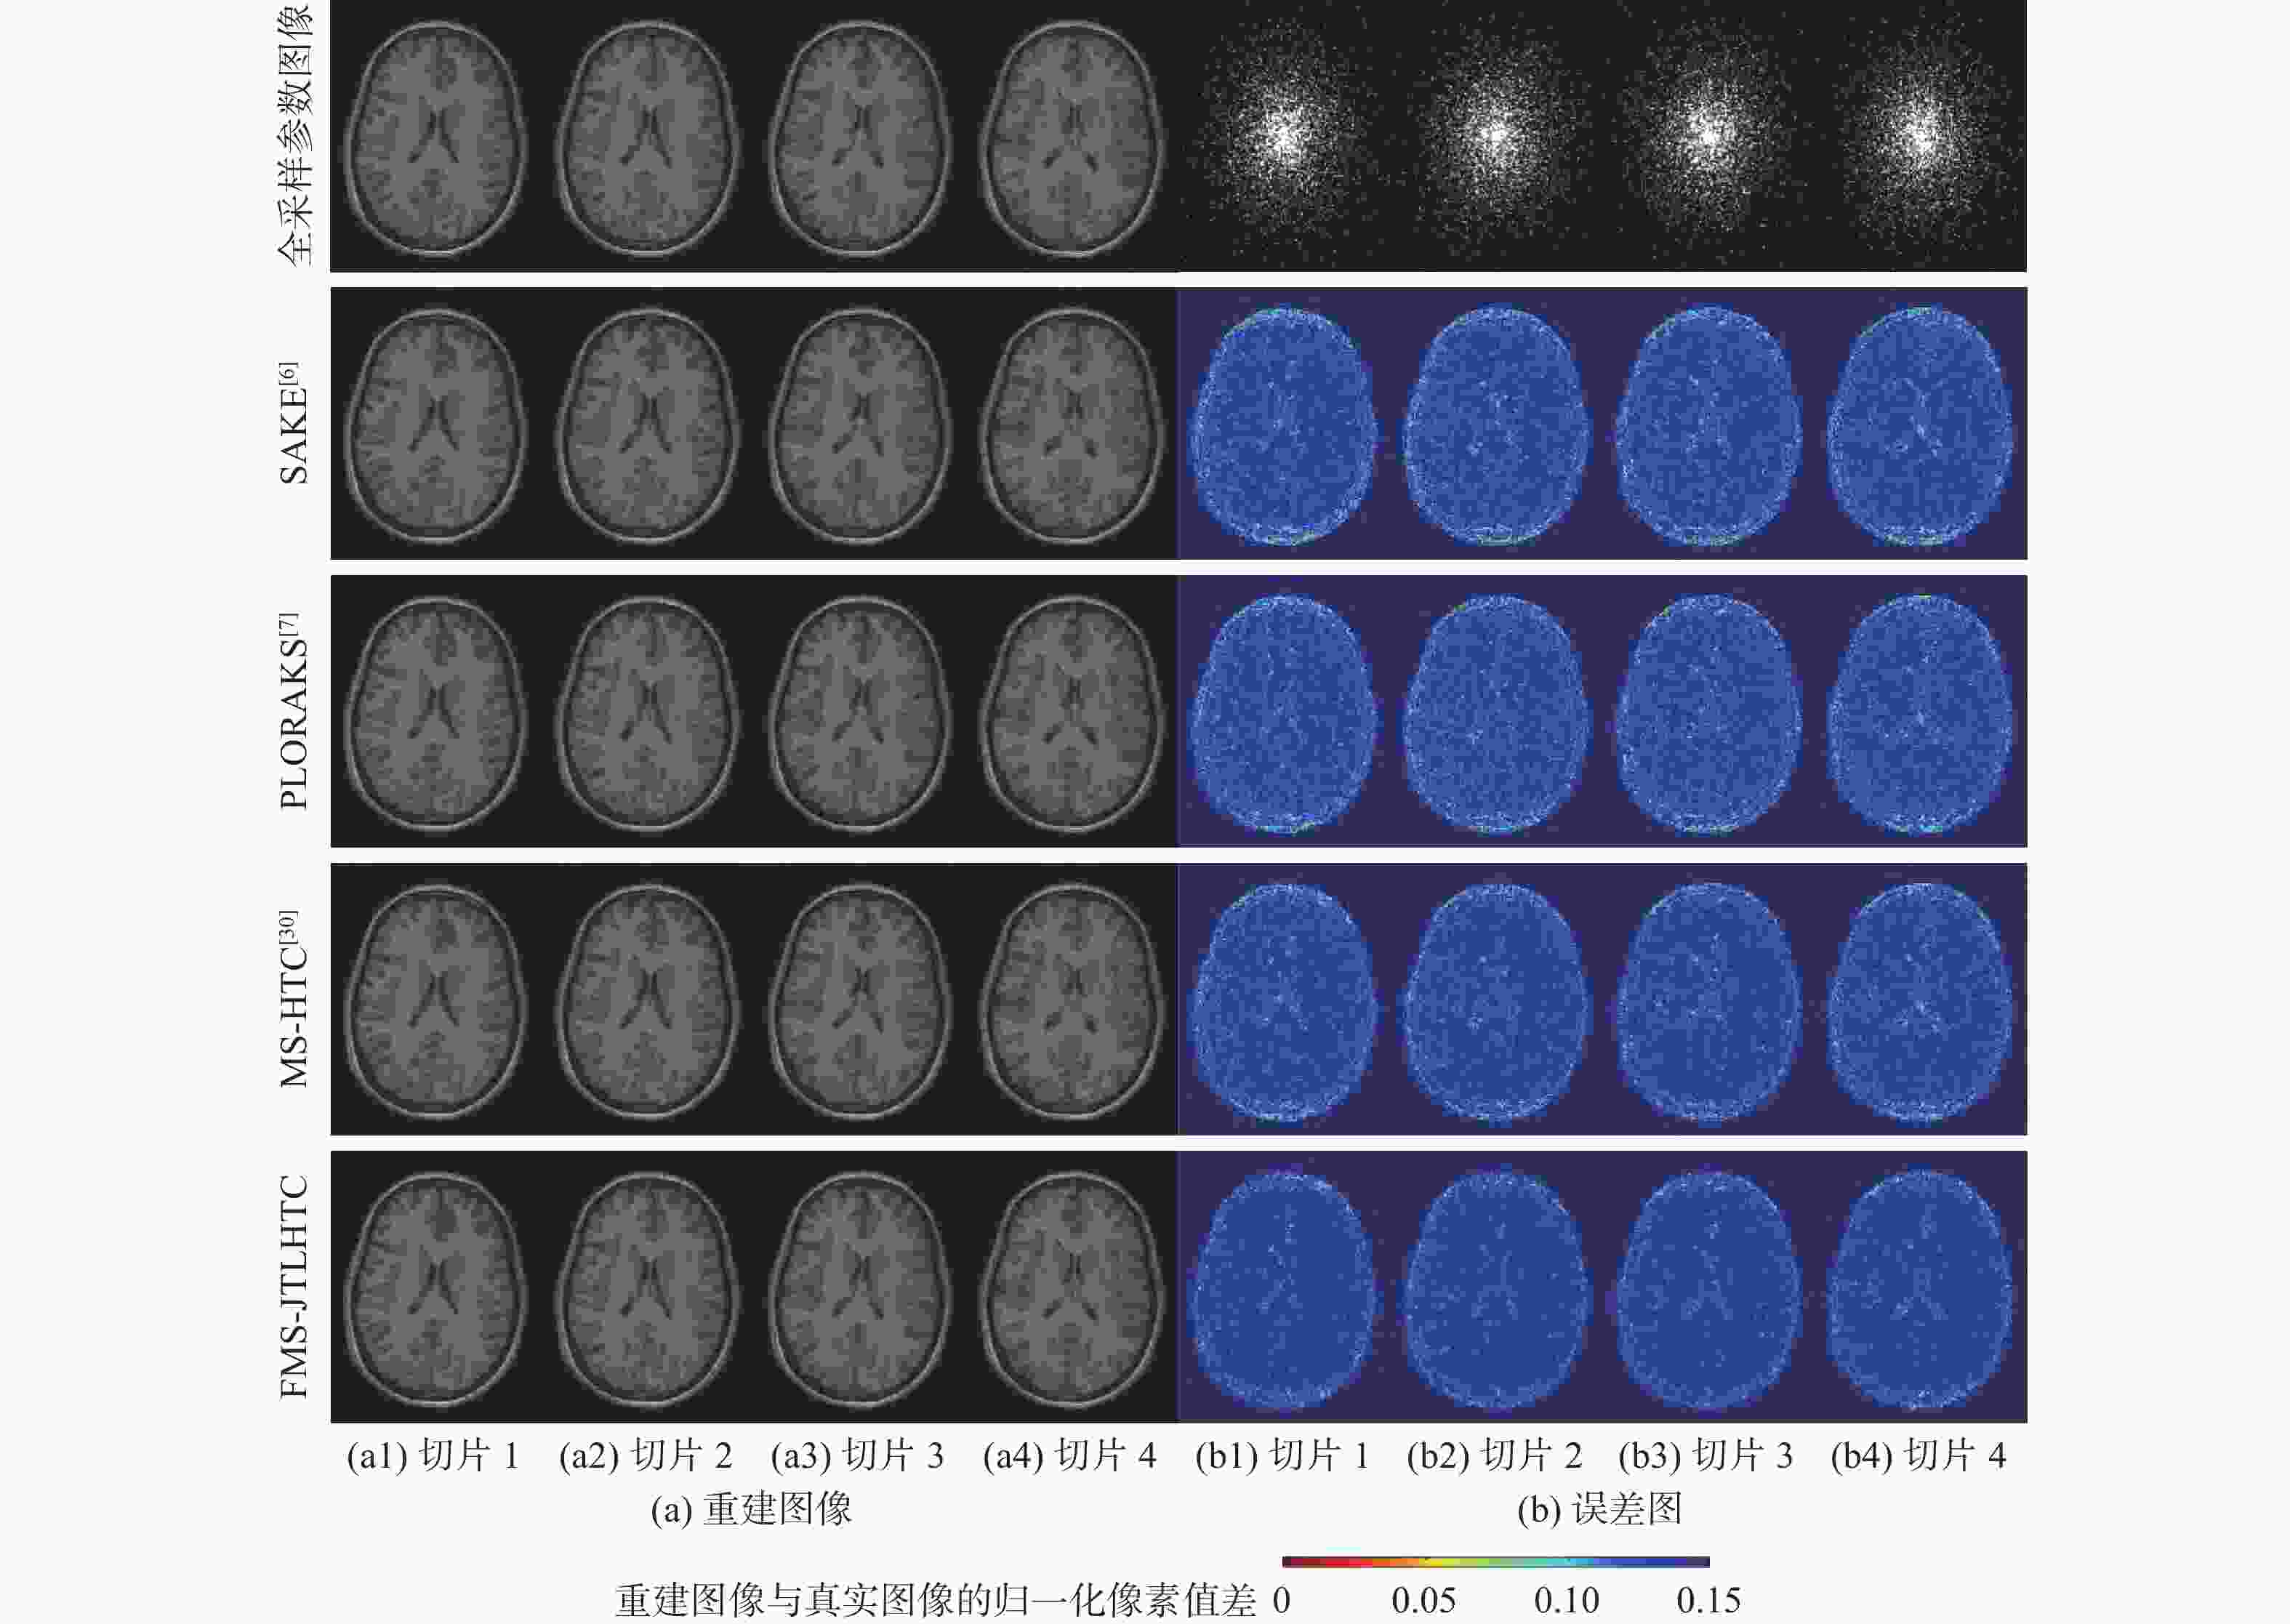

二维(2D)多切片磁共振数据在相邻切片之间具有高度的相关性,通过利用切片间的冗余性能够重建出更高质量的切片图像,但由于硬件条件的限制,2D多切片磁共振成像(MRI)需要耗费大量时间。为提高2D多切片磁共振图像的重建质量和重建速度,将联合稀疏变换学习正则项引入到多切片Hankel张量完成(MS-HTC)模型中,提出一种快速2D多切片磁共振成像重建(FMS-JTLHTC)算法。该算法使用交替方向乘子法对目标问题进行求解;引入快速迭代收缩阈值法加快收敛,并使用图形处理器对算法进行加速。使用4组脑部数据集在2种不同采样模式下进行实验,结果表明:FMS-JTLHTC算法的峰值信噪比(PSNR)相较于同时自动校准和K空间估计(SAKE)算法、并行成像数据的局部K空间领域的低秩建模(PLORAKS)算法和MS-HTC算法分别平均提高了4.04 dB、3.67 dB和2.07 dB,而且重建速度相比MS-HTC算法提高了14倍。

Abstract:Due to the significant correlation between neighboring slices in two-dimensional (2D) multi-slice magnetic resonance data, higher quality slice pictures can be reconstructed by taking use of the redundancy between slices. However, 2D multi-slice magnetic resonance imaging requires an amount of time. To improve the reconstruction quality and speed of 2D multi-slice (MRI) images, proposes a fast 2D multi-slice MRI reconstruction (FMS-JTLHTC) algorithm, which introduces the joint transform learning regular term into the multi-slice hankel tensor completion (MS-HTC) model. Prior to introducing the fast iterative shrinkage-thresholding procedure to accelerate convergence and utilize the graphics processing unit to speed up the procedure, the alternating direction method of multipliers is used to solve the objective issue. Experiments using four brain datasets in two different sampling modes show that the peak signal-to-noise ratio (PSNR) of the FMS-JTLHTC algorithm is improved by an average of 4.04 dB, 3.67 dB, and 2.07 dB compared to the simultaneous atuo-calibrating and K-space estimation (SAKE), low-rank modeling of local K-space neighborhoods with parallel imaging data (PLORAKS) and MS-HTC algorithms, respectively, the reconstruction speed is improved by a factor of 14 compared to the MS-HTC algorithm.